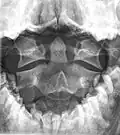

The dens, also called the odontoid process, or the peg, is the most pronounced projecting feature of the axis. The dens exhibits a slight constriction where it joins the main body of the vertebra. The condition where the dens is separated from the body of the axis is called os odontoideum and may cause nerve and circulation compression syndrome.[1] On its anterior surface is an oval or nearly circular facet for articulation with that on the anterior arch of the atlas. On the back of the neck, and frequently extending on to its lateral surfaces, is a shallow groove for the transverse atlantal ligament which retains the process in position. The apex is pointed and gives attachment to the apical odontoid ligament. Below the apex, the process is somewhat enlarged and presents on either side a rough impression for the attachment of the alar ligament; these ligaments connect the process to the occipital bone.